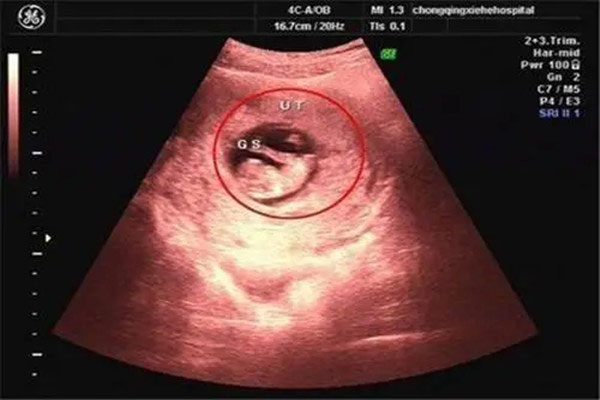

长孕囊和圆孕囊的区别 已生宝妈告诉你答案

长孕囊和圆孕囊的区别 怀孕早期的孕囊,可以看出男孩女孩,很多过来人都是这么说的。其实,关于生男生女的说法,网络上不知道流传着多少呢?但是真正靠谱的却是很少的。网..